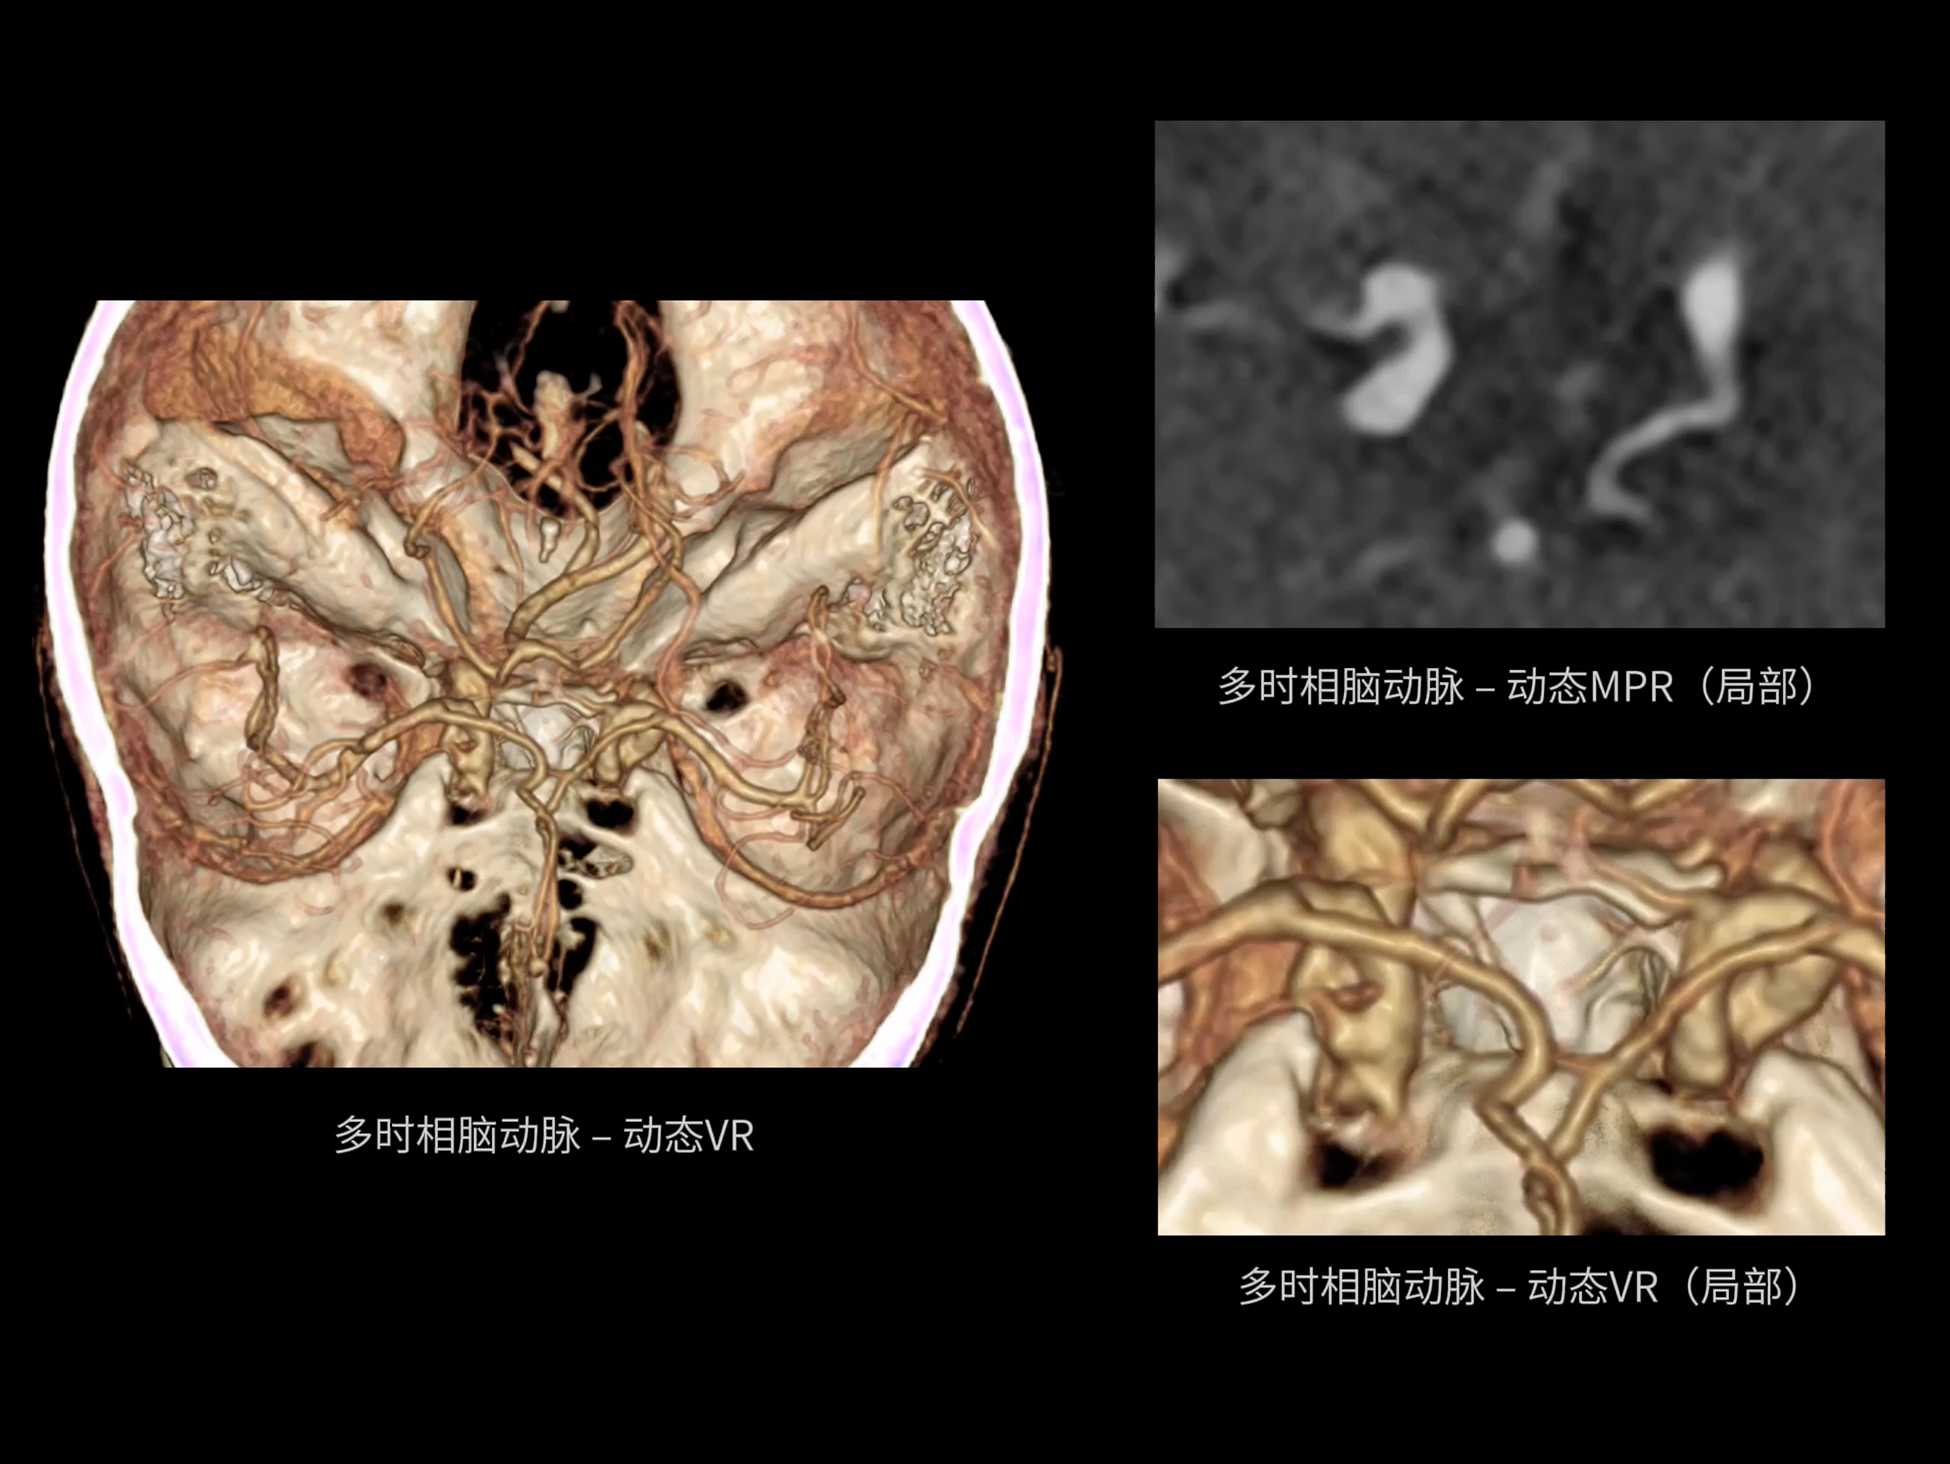

全身各部位动态CT成像

uCT SiriuX® 以16cm超宽Z轴覆盖,使超高时间分辨率应用于完整器官成像。无论是心脏搏动还是关节运动,整个目标区域可在同一瞬时被完整、清晰地捕捉,彻底消除时序误差,实现从“局部瞬间”到“全器官瞬时”的成像跨越。

全器官同步

uCT SiriuX® 以全新双宽体系统架构,同步实现超高时间分辨率与宽体容积覆盖兼得,全面释放性能潜能,敏锐捕捉人体生理运动全景,带来动态影像新视角。

巅峰系统形态

双宽体“零”噪声时空探测器,Z 方向覆盖达16 cm,单圈即可完整扫描头颅、心脏等关键器官,结合超高时间分辨率,可实现真正意义上的全身各部位高清动态成像,让每一次扫描都更高效、更精准。